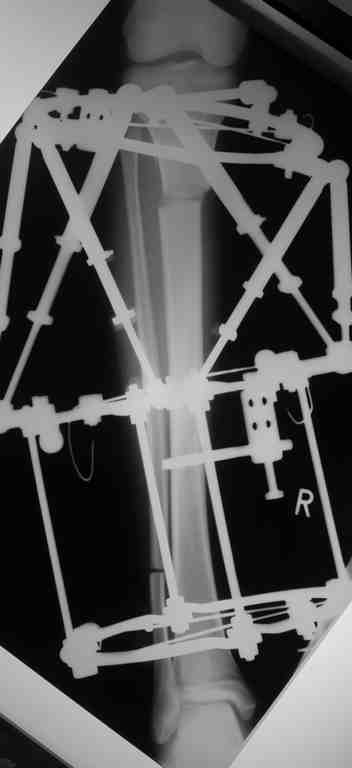

Выше приведены рентгенограммы 13-летнего подростка, страдающего от огнестрельного многооскольчатого перелома дистальной трети бедра. AO наружный фиксатор наложенный в день травмы не дал приемлемой редукции. Через три недели после перелома аппарат Илизарова был наложен без попытки одномоментной репозиции на операционном столе.

There are X-Rays of a thirteen year old boy with a comminuted distal femur fracture secondary to a gunshot wound, initially treated with an AO external fixator. The alignment was unacceptable and an Ilizarov external fixator was applied three weeks after the injury. No attempt of definitive reduction was made during the surgery.

Гексаподная приставки наложена на 10 дней и приемлемая редукция была получена.

The Hexapod set was applied for ten days and acceptable reduction was received.

По окончанию редукции Гексаподный сет был снят и дальнейшее ведение больного проходило в стандартном режиме аппарата Илизарова. Хороший анатомо-функциональный результат был получен.

When reduction was finished, the Hexapod set was removed and further management has been continued by standard Ilizarov regime. Good anatomic and functional results were achieved.